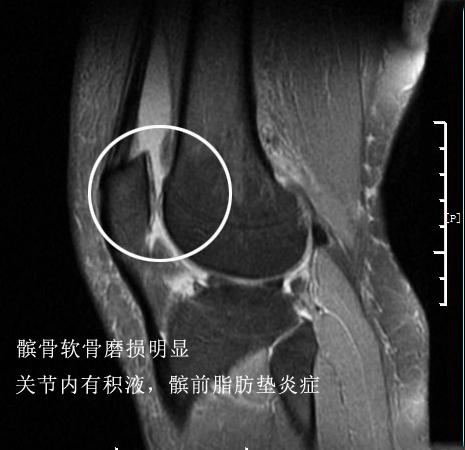

当我详细的询问了患者的症状以后,给她做了细致的查体,除了她有明显的髌骨软骨磨损体征外,判断半月板损伤的麦氏征查体却是阴性的,关节积液查体存在阳性,但不是很多,令我印象深刻的是她关节的皮肤热乎乎的,这是常见于长时间热敷关节患者的体征,代表着关节内无菌性炎症较重。鉴于她当时的核磁是于当地医院检查的并不特别清晰,我好好的安慰了一下她之后,给她复查了核磁。

而结果和我想的一样,关节内除了髌骨软骨有轻度的磨损、髌前脂肪垫有无菌性炎症以外,半月板、韧带以及关节软骨并没有发现特别严重的病情,这个患者的病情并不严重。绝对达不到她目前的这个状态。

根据她的情况,我详细的给她讲解了核磁片子,告诉她半月板并没有那么严重的损伤,但是关节内的软骨有了轻度的磨损,她完全可以行走,不用担心会把半月板撕裂,而且适度的活动会帮助她更好的恢复,完全没有必要一动不动。